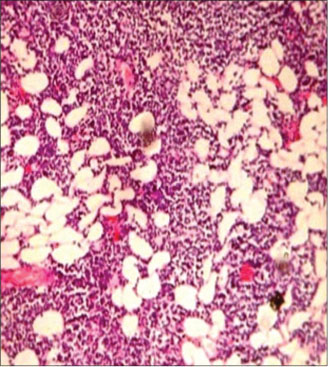

On histopathological examination, soft-tissue tumor showed the monomorphic population of large plasmablastic cells with abundant basophilic cytoplasm. Round to ovoid vesicular nuclei with prominent peripheral-based nucleoli. Prominent tingible body macrophages seen imparting a starry-sky appearance with prominent mitotic activity suggestive of plasmablastic lymphoma.

Dignosis was confirmed on IHC and tumor cells were positive for CD138, EMA, LCA, and negative for CD20, CD56, CK, S100, NSE, synaptophysin, and chromogranin [Figure 8].

|?Figure. 8? A Prominent tingible body macrophages, imparting a starry-sky appearance with prominent mitotic activity, monomorphic population of large plasmablastic cells with abundant basophilic cytoplasm, and prominent peripheral-based nucleoli - Plasmablastic Lymphoma - (H and E, ?100), IHC ? Positive ? EMA, LCA, CD138

Plasmablastic lymphoma is a rare and rapidly progressive variety of DLBL that was originally reported exclusively in the jaw and oral mucosa of male-predominant HIV-positive patients. A substantial minority of cases occur in HIV-negative patients following solid organ transplantation or immunosuppressive therapy.